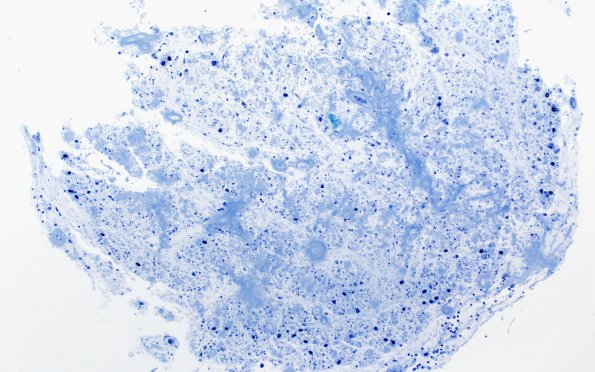

9D1-3 One micron-thick, toluidine blue stained sections show at least two fascicles with near complete loss of large and small myelinated axons, consistent with end stage nerve. Again, much of the endoneurial space is occupied by amyloid and many blood vessels show mural thickening by amyloid deposition. (Plastic sections)